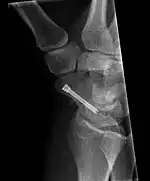

Scaphoid fracture before and after operation

The scaphoid can be slow to heal because of the limited circulation to the bone. Fractures of the scaphoid must be recognized and treated quickly, as prompt treatment by immobilization or surgical fixation increases the likelihood of the bone healing in anatomic alignment, thus avoiding mal-union or non-union.[6] Delays may compromise healing. Failure of the fracture to heal ("non-union") will lead to post-traumatic osteoarthritis of the carpus.[1]:189 One reason for this is because of the "tenuous" blood supply to the proximal segment.[3] Even rapidly immobilized fractures may require surgical treatment, including use of a headless compression screw such as the Herbert screw to bind the two halves together.

Scaphoid fractures may be difficult to diagnose via plain x-ray. A repeat x-ray may be required at a later date, as might cross-sectional imaging via MRI or CT scan.[6]